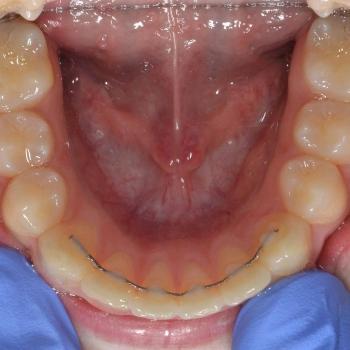

Dávid és szülei a felső fogív súlyos torlódása, illetve az alsó állcsont alulfejlettsége miatt keresték fel a rendelésem. Az első konzultáció alkalmával ezen felül Angle II-es harapási eltéréssel, nyitottharapással, a felső fogív keresztirányú szűkületével, az alsó középvonal súlyos eltolódásával, illetve bal alsó maradó szemfog számára szükséges hely teljes hiányával találkoztunk.

A kezelési terv mindezen problémák figyelembevételével a Dávidék által választott hagyományos fém fogszabályozót, hyrax készüléket (a felső fogív tágítására), fejtetői húzású headgeart (a nyitottharapás kezelésére), stripelést és különböző intermaxilláris gumihúzásokat tartalmazott.

Az eltérések súlyossága ellenére, a szinte tökéletes kooperációnak köszönhetően foghúzás nélkül egy funkcionálisan és esztétikailag is szép eredménnyel zárhattuk a kezelést.